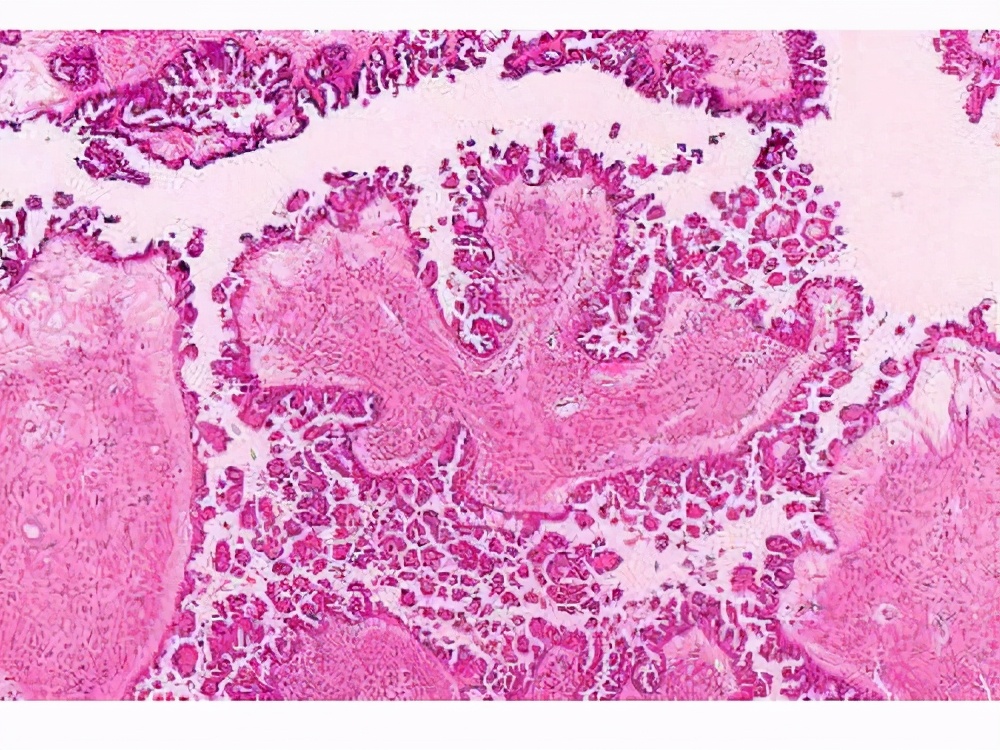

何为交界性恶性肿瘤

关于交界性肿瘤的概念,起初是用来描述卵巢的上皮性肿瘤。这个概念在1961年被正式提出,并于1973年由世卫组织正式采用。对它的认识,可以追溯到20世纪50年代。当时发现在宫颈鳞状上皮细胞癌发生之前,鳞状上皮出现了一系列由轻-重度的不典型增生和原位癌,以后称为CIN Ⅰ--Ⅲ级。良性和恶性之间交界性病变有许多不同名词:比如不典型增生 、异型增生、癌前病变、恶性前病变、低恶性潜能、恶性潜能不肯定、交界恶性中间恶性以及上皮内肿瘤等。

以上名词确切的涵义可能不完全相同。但总的来讲,就是指不是明确的良性,亦非肯定的恶性,价于两者之间的病变,所以统称为交界性病变。目前真正用于诊断的除卵巢表面上皮-间质起源的肿瘤有明确的交界性肿瘤外,还未用于其它肿瘤。随着近年来科学技术特别是医学生物学的快速发展,大量有关病例和随访结果的日积月累,人们开始发现和认识到越来越多的交界性肿瘤。但世界卫生组织《疾病和有关健康问题的国际统计分类》(ICD-10)中真正命名的交界性肿瘤数量还是比较有限的,并不能满足所有恶性肿瘤的诊断和命名需求。所以恶性肿瘤,尤其是未定性肿瘤的诊断在临床上是另很多医生头疼的问题,而关于恶性肿瘤的疾病编码使用以及分类也是很多核心医学期刊文章的重点讨论内容。

交界性恶性肿瘤的特点

一、在临床肿瘤病理诊断工作中,交界性肿瘤是一大难点。

交界性肿瘤概念的出现,使肿瘤分类免于非良即恶的绝对化,使人们将肿瘤性质确切地理解为由良性至潜在恶性至低度恶性至高度恶性这一系列梯度式分布,这样对肿瘤患者治疗方法更加合理适当,但是对病理医师的确是一大挑战。临床医师通常最希望能提供明确诊断为“良性”或“恶性”肿瘤或病变的病理报告,甚而有些人只关心病理报告的最后一个字:“癌”还是“瘤”。但必须指出,对于病理报告的这种简单化的认识是不合适的。临床医师也需要认识和理解“交界性肿瘤”的病理诊断,并非“模棱两可”的诊断,并非病理医师限于诊断水平做出的权宜之计。一般说来,对交界性肿瘤及交界性病变病理诊断的正确应用是病理医师高水平的体现。对于病理医师来说,应以严肃负责的态度作出关于交界性肿瘤的诊断。